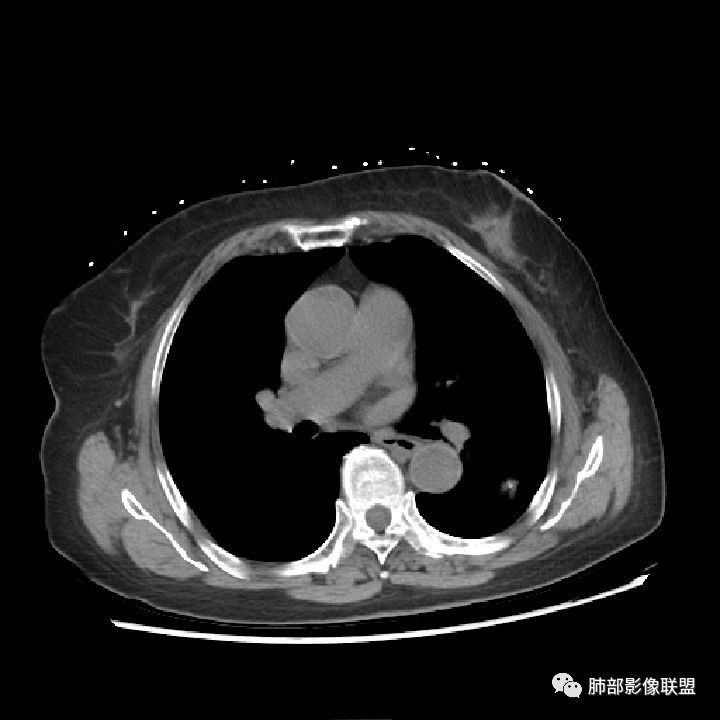

看了薄层我也倾向于恶性肿瘤。叶间裂牵拉比较明显了,分叶,胸膜凹陷,周围清晰磨玻璃,支气管也闭了。

这属于瘢痕癌,有炎性特点,有长索条影,有钙化,血管进入,比较自如,边缘似乎有点毛糙,有长索条影,有恶性特点,大家都关注钙化了,关注边缘收缩了,

南边:这类病变,其实我们读了很多了。属于什么样的病变,属于瘢痕癌。我先标注给大家看一下,这个良恶性特点在哪里:

南边:首先,他有炎性的特点,有长索条吧,还有一个大的钙化。对不对,血管进去里面走行也自如,边缘似乎有点毛糙,但是没有薄层,不是很好看。

南边:它符合一个纤维索条影的一些病变存在的特点,为什么,有长索条边缘是吧,近端也是。

南边:但是它也有很多恶性的特点,大家没注意而已,大家把精力所有的关注在哪里?关注钙化灶里面去了,关注在纵隔窗的一个边缘收缩去了。

南边:你看看这个主体层面,大的一些层面,看看纵隔窗跟肺窗一对比,就发现病变不密实,似乎缩小了一大半,这就不正常了。

1.肺部结节多钙化,常常是良性病灶的象征之一。如结核、错构瘤等。肺癌钙化不多见,如小细胞肺癌的钙化椒盐样分布,转移瘤结节常随机且多发等等。

2.本例肺结节内部钙化影规整而密实,既不同于错构瘤的“爆米花”或“桑葚”铺展,又有别于结核球的典型的同心圆样排布。

3.如我们无视这一钙化灶,结节影却似乎表现出另一副面孔,实性成份较多,边缘不规则,居然有磨玻璃有分叶、有异常供血、有棘状突起有胸膜牵拉等。病灶孤立,不像错构瘤静悄悄悬挂血管旁,亦未如结核球那样多卫星灶。

4.注意增强扫描,实性部分有较明显强化,这无论在结核球或是错构瘤都非常少见。

5.肺部钙化灶原本常见。肺组织并不会因为局部钙化灶的存在而豁免新生物。